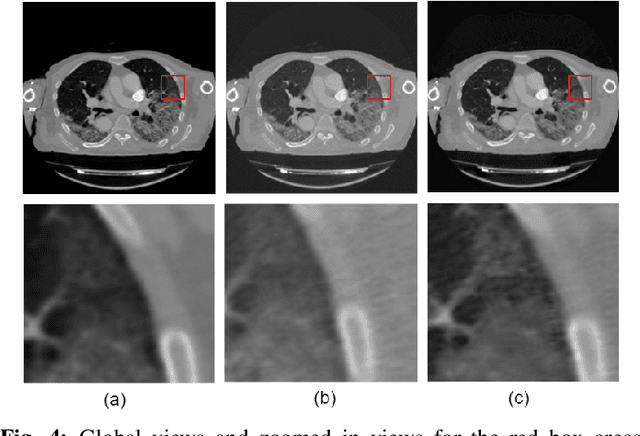

Abstract:We present a deep-learning based computing framework for fast-and-accurate CT (DL-FACT) testing of COVID-19. Our CT-based DL framework was developed to improve the testing speed and accuracy of COVID-19 (plus its variants) via a DL-based approach for CT image enhancement and classification. The image enhancement network is adapted from DDnet, short for DenseNet and Deconvolution based network. To demonstrate its speed and accuracy, we evaluated DL-FACT across several sources of COVID-19 CT images. Our results show that DL-FACT can significantly shorten the turnaround time from days to minutes and improve the COVID-19 testing accuracy up to 91%. DL-FACT could be used as a software tool for medical professionals in diagnosing and monitoring COVID-19.